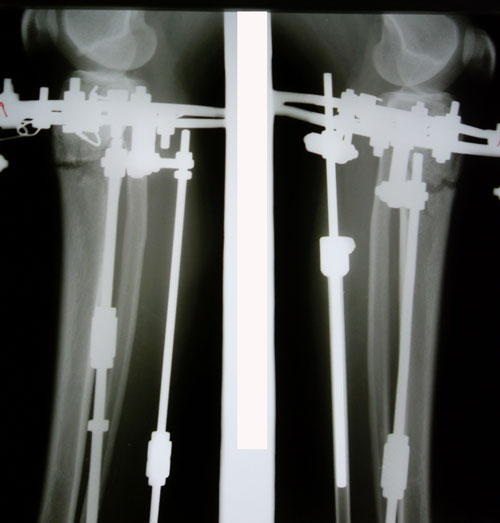

Понедельник , 20-ый день со дня операции. Сегодня мои ножки отдыхают от круток. С утра к нам пришел мастер по маникюру и педикюру ну и мы не задумываясь воспользовались ее услугами! Привели в порядок свои ноготочки , разнообразили наши будние дни и немного подняли себе настроение!

. После обеда я собралась в путь дорогу на первый этаж для снятия рентгена, а для этого мне необходимо преодолеть спуск по лестнице

я даже представить не могла как буду это делать ...но оказывается БОЛЬШЕ БОЯЛАСЬ .. Спуск и подъем по лестнице преодолела спокойно и безболезненно, конечно же не без помощи нашей любимой и отзывчивой Мариши ! Она ни на шаг не отходила от меня и всю дорогу подстраховывала! Гляжу на свои снимки и не могу поверить , что это мои косточки !!! Просто фантастика!

. Посмотрим что завтра скажет Николай Николаевич .....

На фиксации.